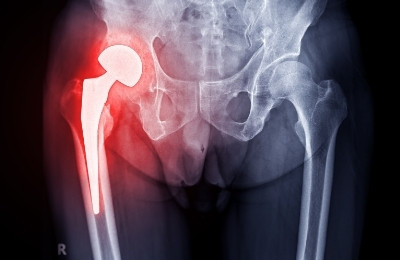

Hip Revision Surgery

An old hip replacement shouldn’t become a new source of pain. If your implant has worn out, loosened, or failed, Dr. Mehta offers hip revision surgery tailored to your anatomy and previous surgical history, restoring strength, function, and confidence with expert care.